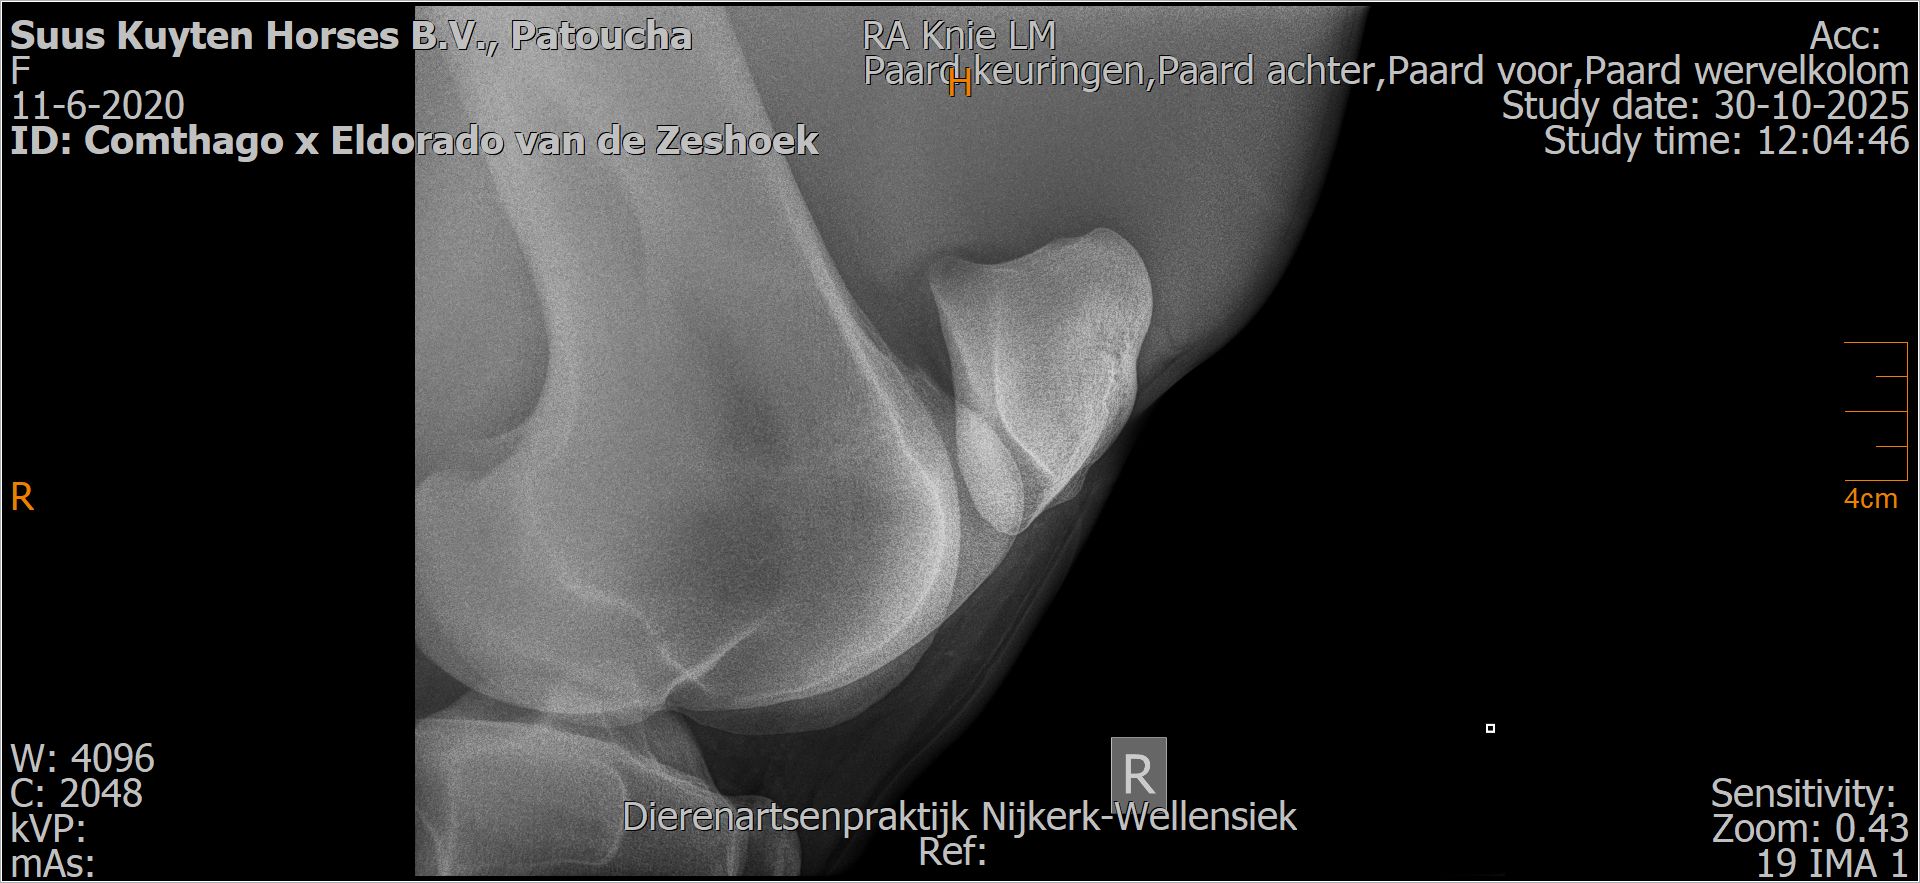

Patoucha

Leeftijd:

7

Röntgenfoto’s